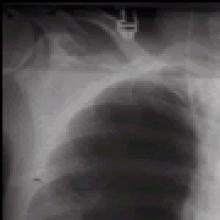

| Figure 1. Large right-upper lobe lucency |

The patient was afebrile and hemodynamically stable. However, pulse oximetry registered 70% as the patient was receiving 4 liters of oxygen by nasal canula. On physical examination, the patient had diminished breath sounds in the right-upper chest and diffuse expiratory wheezing. An arterial blood gas (ABG) in the ED revealed a pH 7.23, PaCO2 126 mm Hg, PaO2 37 mm Hg and SaO2 72%. An admission chest roentogram was obtained and revealed a large right-upper lobe lucency without evidence of pneumothorax (Figure 1). The patient was endotracheally intubated in the ED for respiratory distress, and a repeat ABG (pH 7.39, PaCO2 83 mm Hg, PaO2 160 mm Hg and SaO2 92%) on ventilator settings of tidal volume 500 ml, no positive end-expiratory pressure, respiratory rate of 20 breaths per minute and 50% FiO2 showed improvement. Following intubation, the patient was admitted to the MICU and aggressive pulmonary therapy was pursued. Intravenous steroids, frequent nebulizers and intravenous antibiotics were also administered. Chest computed tomography (CT) demonstrated a massive right apical bulla occupying nearly one-third of the right hemithorax along with several smaller bullae seen throughout the right and left lungs (Figure 2). The patient subsequently improved, and was able to be extubated on the morning of the second hospital day. A post-extubation ABG on 2 liters of oxygen by nasal canula was pH 7.36, PaCO2 85 mm Hg, PaO2 55 mm Hg and SaO2 85%. Pulmonary function tests (PFTs) revealed an FEV1 of 0.39 liters (9% of predicted) and a FVC of 0.8 liters (16% of predicted).